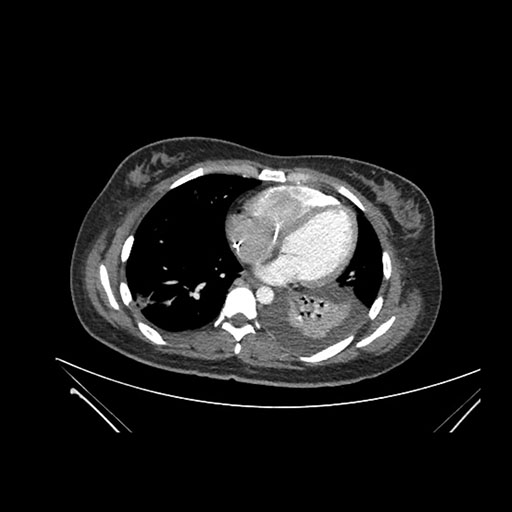

Axial Arterial

Axial Venous

Imaging analysis

Based on initial findings, which issue(s) would you be most concerned about?